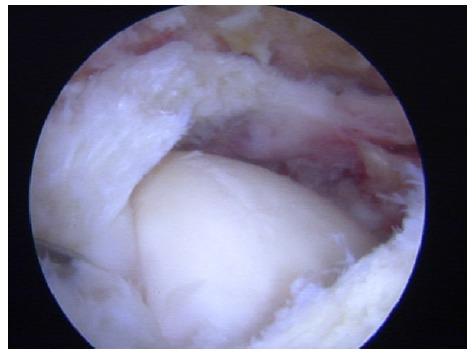

The glenohumeral joint is a ball-and-socket joint that is inherently unstable and thus, susceptible to dislocation. The traditional and most common anatomic finding is the Bankart lesion (anterior-inferior capsule labral complex avulsion), but there is a wide variety of anatomic alterations that can cause shoulder instability or may be present as a concomitant injury or in combination, including bone loss (glenoid or humeral head), complex capsule-labral tears, rotator cuff tears, Kim´s lesions (injuries to the posterior-inferior labrum) and rotator interval pathology.

Due to the complex anatomy of the shoulder and the large range of movement of this joint, a wide variety of anatomic injuries and conditions can lead to shoulder instability, specially present in young population. Recognizing and treating all of them including Bankart repair, capsule-labral plicatures, SLAP repair, circumferential approach to pan-labral lesions, rotator interval closure, rotator cuff injuries and HAGL lesion repair is crucial to achieve the goal of a stable, full range of movement and not painful joint.

盂肱关节是球窝关节,本质上不稳定,因此易发生脱位。传统且最常见的解剖学发现是Bankart损伤(前下关节囊盂唇复合体撕脱),但存在多种可导致肩部不稳定或可能作为伴随损伤出现或合并存在的解剖学改变,包括骨质流失(肩胛盂或肱骨头)、复杂的关节囊盂唇撕裂、肩袖撕裂、Kim损伤(后下盂唇损伤)和旋转间隙病变。

由于肩部解剖结构复杂且该关节活动范围大,多种解剖学损伤和病症可导致肩部不稳定,尤其在年轻人群中常见。识别并治疗所有这些损伤,包括Bankart修复、关节囊盂唇折叠术、SLAP修复、全盂唇病变的圆周入路、旋转间隙闭合、肩袖损伤和HAGL损伤修复,对于实现稳定、全范围活动且无痛关节的目标至关重要。